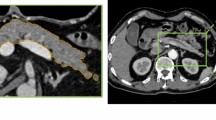

CPR images were obtained based on the pancreatic phase images, which were obtained 20 s following the first scan. Manually created CPR images were generated by one of 10 radiology technicians from our institution who were experienced in the task (at least 30 cases). Images were generated on the operator console of the CT system. They traced the pancreatic duct centerline in the axial image, reconstructed it, and finally generated a single CPR image along the MPD (Fig. 2).

Generation of automatic CPR images

The automatic CPR images were created using software under development (Fig. 3), which encompasses three processes: pancreas segmentation, pancreatic duct segmentation, and pancreatic duct centerline detection.

The whole pancreatic region was segmented by a 3D convolutional neural network (3D-CNN) based on U-net. A total of 290 cases from the TCIA and MSD were used for training. In addition, 73 cases from the TCIA and MSD were used for validation of pancreas segmentation.

Pancreatic duct segmentation was also performed using 3D-CNN based on U-net: 148 cases from the MSD were used for training. Furthermore, 12 cases from the MSD were used for validation of pancreatic duct segmentation.

The pancreatic duct centerline was detected by conventional image processing. The optimal pathway was searched from the pancreatic head to tail by employing Dijkstra’s routing algorithm, followed by the identification of the pancreatic duct centerline. The pancreatic duct centerline was defined as follows: (a) it passes through the segmented pancreatic duct, or (b) passes approximately through the center of the segmented pancreas if the MPD was undetectable in pancreatic duct segmentation.